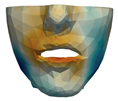

2.5.2. Soft Tissue

2.6. Textured Output Visualization